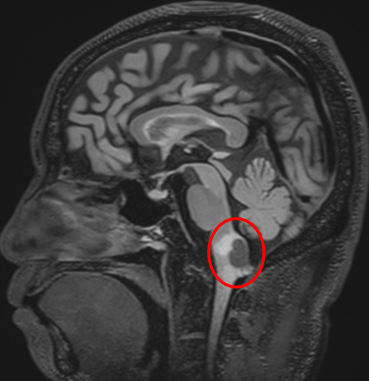

在中国工作生活多年的Z先生,因身体麻木查出“延髓背侧占位”,最终选择在亚洲神经外科临床、科研、教学基地——北京天坛医院,由国际脑干大咖巴教授主刀手术。

北京时间2025年8月13日,巴教授采用枕下正中入路为Z先生成功实施了肿瘤全切手术。整台手术如预期般顺利——这源于巴教授三十余年脑干领域的深厚积淀与精湛技艺。两位德国人在中国的相遇,交流格外顺畅——从术前沟通到术后恢复,Z先生一直用德语与巴教授沟通。麻醉清醒后,他第一时间用德语向教授反馈自己的情况。术后情况如此之好,Z先生难掩欣喜,特别感谢巴教授团队和天坛医院帮他消除了这个可怕的脑瘤。

延髓背侧是脑干最尾端的关键区域,厚度仅约1.5-2cm,却密集排列着调节呼吸(如延髓背侧呼吸组)、心血管(如孤束核参与压力反射)和消化功能的核团。手术器械的轻微偏移(甚至1-2mm)即可损伤生命中枢。

小脑后下动脉(PICA)及其穿支血管在该区域形成迂曲的“血管丛林”,供应延髓的同时,其损伤可能导致延髓背侧梗死(如Wallenberg综合征)。更棘手的是该区域的常见病变,如血管母细胞瘤富含异常血供,稍有不慎就会引发难以控制的出血。